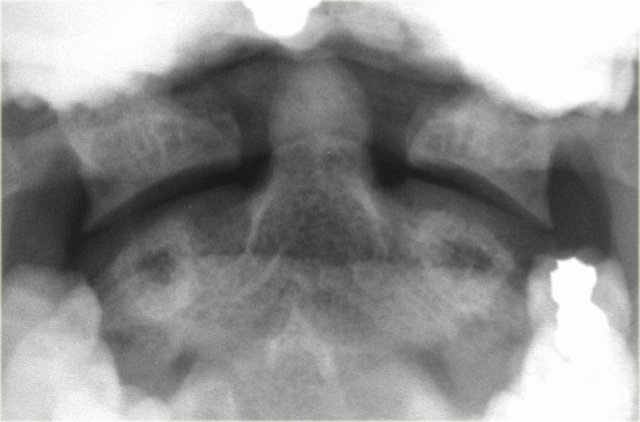

On the left the most common type of odontoid fracture, which is type II through the base of the odontoid.

These type II fractures have a tendency to nonunion, which occurs in 64%.

On the left another type II odontoid fracture.

Sometimes these fracture-lines can be difficult to see.

There are fracture mimics like lucent lines as a result of overprojection or a prominent mach line (figure).